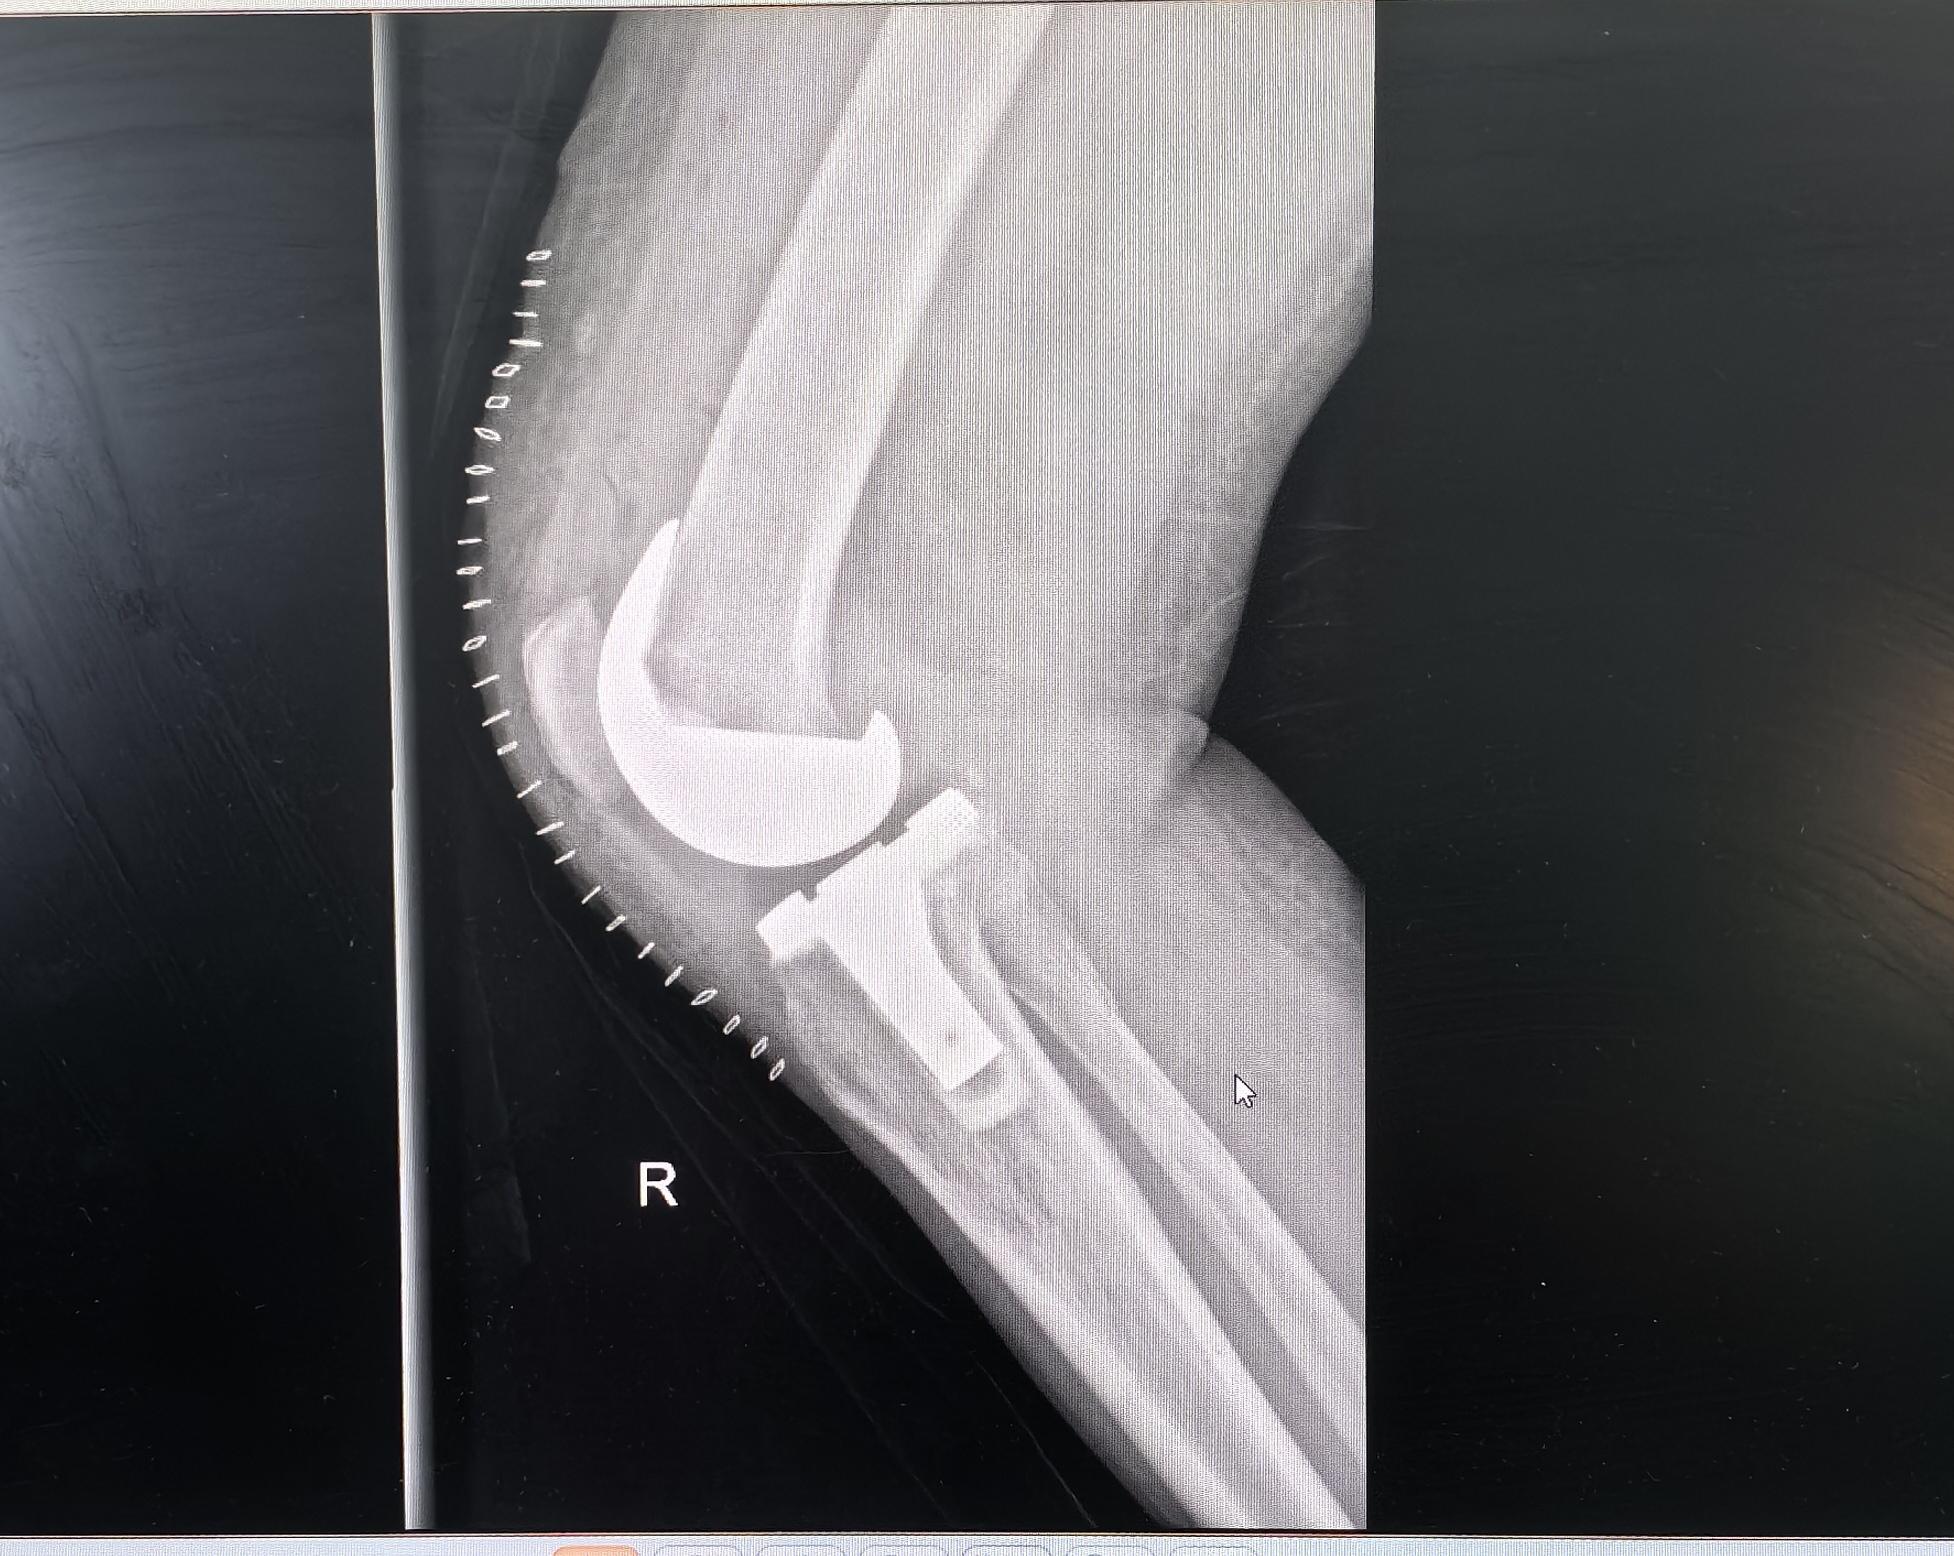

膝关节置换,类风湿关节炎。类风湿关节炎,屈曲挛缩合并外翻畸形